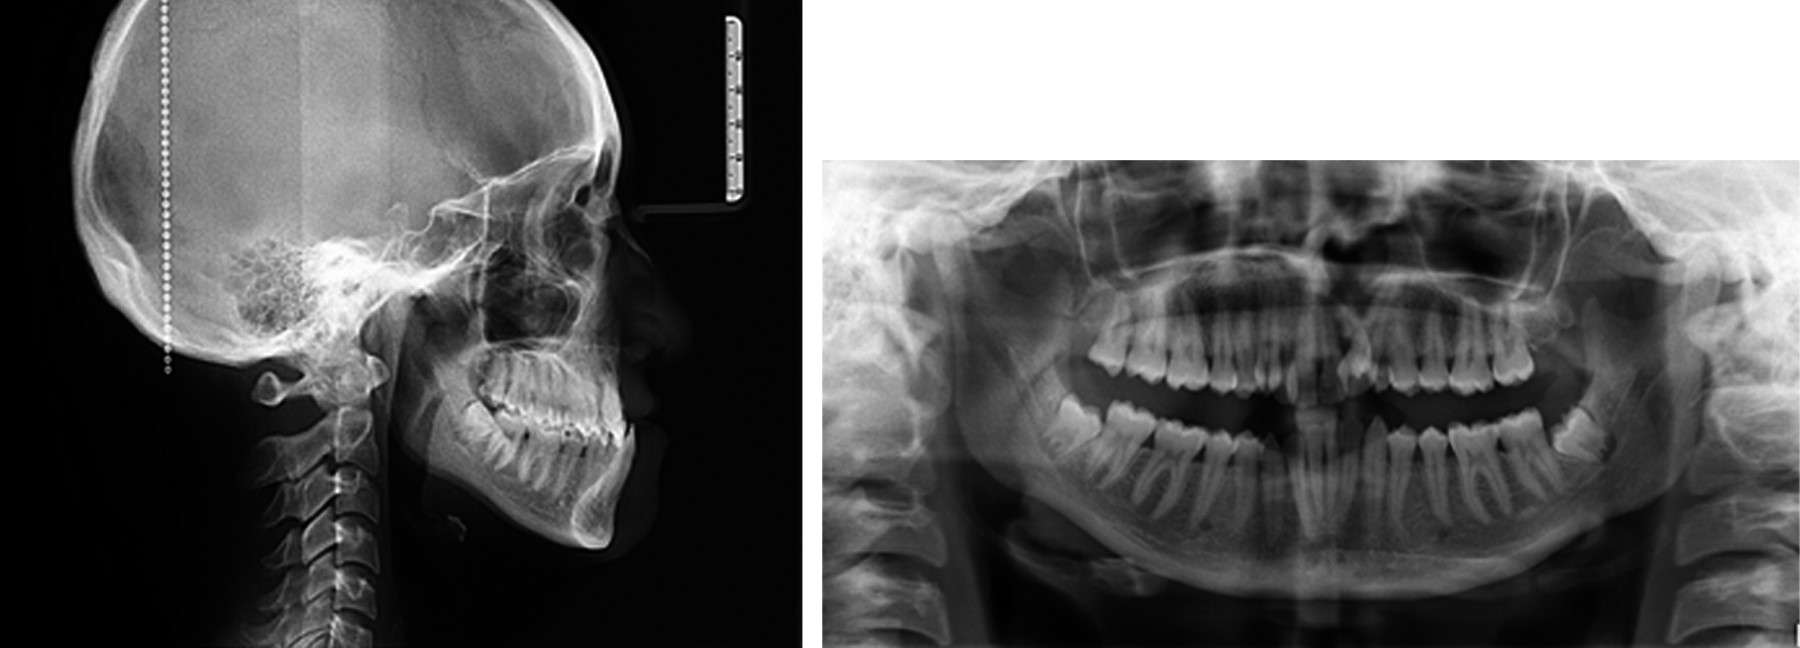

Se reporta un caso clínico de paciente femenino de 23 años con secuela de labio y paladar hendido, clase III dentoesqueletal, dolicofacial, crecimiento hiperdivergente, perfil cóncavo, plano oclusal canteado, laterognasia mandibular, mordida cruzada anterior y posterior, comunicación oronasal a nivel del canino superior izquierdo, lado derecho con clase I molar y clase I canina, lado izquierdo clase I molar, clase canina no valorable (Figuras 1 y 2).

En la fase prequirúrgica se le colocó sistema Roth 0.022", se realizaron extracciones de OD 12 y 22, VTO y TPQ inicial. Se descompensó y se preparó para la cirugía ortognática (Figuras 3 y 4).